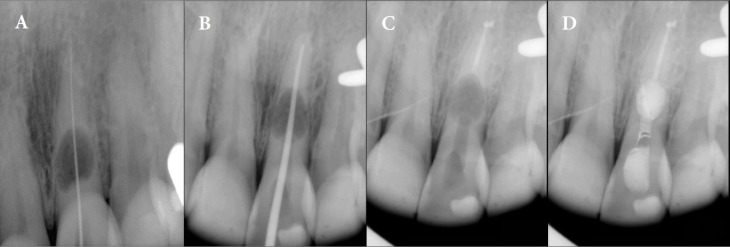

Internal inflammatory root resorption (IRR) poses significant challenges in endodontic treatment due to its potential to compromise tooth integrity. This case report describes the conservative management of IRR in a 40-year-old woman with a radiolucent lesion in the midroot of a maxillary central incisor. Early diagnosis using cone-beam computed tomography prevented perforation and guided treatment planning. Non-surgical endodontic treatment was performed using a dental operating microscope, ultrasonic irrigation, and a hybrid obturation technique. The apical portion of the canal was sealed with a bioceramic sealer and single-cone gutta-percha, while the resorptive defect was filled with calcium-enriched mixture cement due to its biocompatibility and sealing properties. At one-year follow-up, the patient was asymptomatic, with radiographic evidence of healing. This case highlights the efficacy of combining advanced diagnostic tools, bioactive materials, and minimally invasive techniques for successful IRR management.